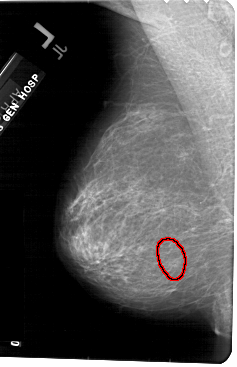

A_1562_1.LEFT_CC

LEFT_CC LINES 5491 PIXELS_PER_LINE 3301 BITS_PER_PIXEL 12 RESOLUTION 43.5 OVERLAY

FILE: A_1562_1.LEFT_CC.OVERLAY

TOTAL_ABNORMALITIES 1

ABNORMALITY 1

LESION_TYPE CALCIFICATION TYPE AMORPHOUS DISTRIBUTION CLUSTERED

ASSESSMENT 4

SUBTLETY 3

PATHOLOGY BENIGN

TOTAL_OUTLINES 1